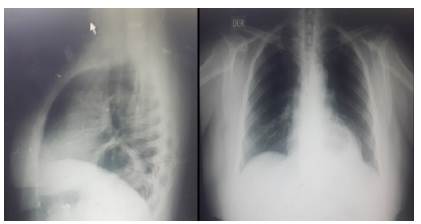

Paciente femenino, 52 años de edad, que consulta por dolor de 12 horas de evolución tipo cólico, urente, en hipocondrio izquierdo, intensidad 8/10 según la escala análoga, acompañado de pirosis, náuseas y vómitos de contenido gástrico, irradiado a región lumbar; dos días antes consultó por sintomatología similar, tratada con analgésicos e inhibidores de bomba de protones, sin mejoría; una ecografía de ese momento reportó esteatosis hepática y vesícula biliar ausente. Antecedentes de hipertensión arterial, colecistectomía, cesárea y menopausia precoz. Al examen físico se encontró álgida, pálida, diaforética, abundante panículo adiposo abdominal; dolor a la palpación en epigastrio, mesogástrio e hipocondrio izquierdo, sin más datos importantes; pruebas de laboratorio normales; impresión diagnóstica: enfermedad ácidopéptica. Una esofagogastroduodenos-copia interrogó hernia paraesofágica de 2 cm vs. vólvulo gástrico; una radiografía de tórax evidenció nivel hidroáereo retrocardiaco en la proyección lateral e imagen sugestiva de masa retrocardiaca en la proyección anteroposterior (figura 1).